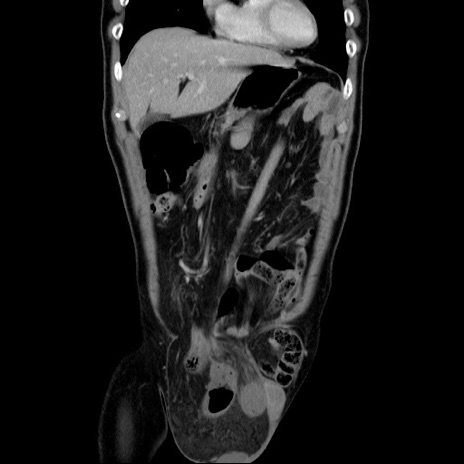

症例34(冠状断像)

【症例】60歳代 男性

【主訴】右鼠径部膨隆

【現病歴】1年程前より右鼠径部膨隆あり。自己にて還納可能だったため放置していた。3時間前より右鼠径部の脱出を認め、還納困難となり受診。

【既往歴】高血圧

【身体所見】右鼠径部に小児頭大の膨隆あり。弾性硬であり、用手還納は困難。左鼠径部にも膨隆を認める。脱出はなし。